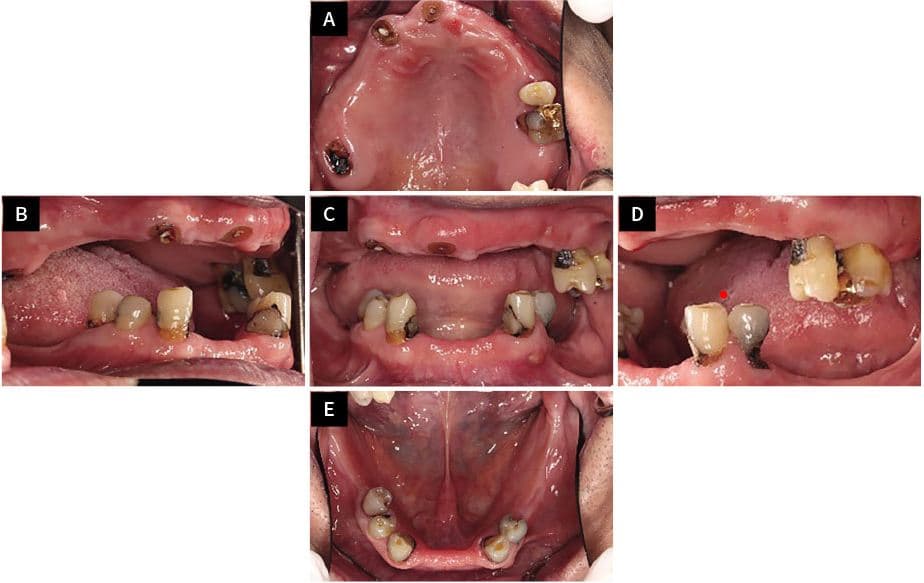

To'liq implant

oldin va keyin

Haqiqiy bemorlarimizning ajoyib o'zgarishlarini ko'ring

After ✨

Kang●● · 50 yoshdan oshgan erkak

Implant + Toj + Ko'prik kombinatsiyasi

Song●● · 60 yoshdan oshgan ayol

Shaxsiy protez kombinatsiyasi davolash

Jo●● · 50 yoshdan oshgan ayol

Tejamkor shaxsiy davolash